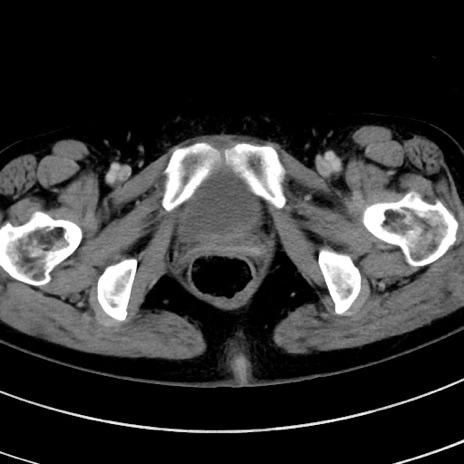

冠状断像

【症例】 60歳代女性

【主訴】むかつき、みぞおちの痛み

【現病歴】3日前よりむかつきがあり、食事がとれない。

【既往歴】糖尿病

【身体所見】発熱なし、心窩部圧痛軽度あるも、腹膜刺激症状なし。

【データ】WBC 7400、CRP 1.92